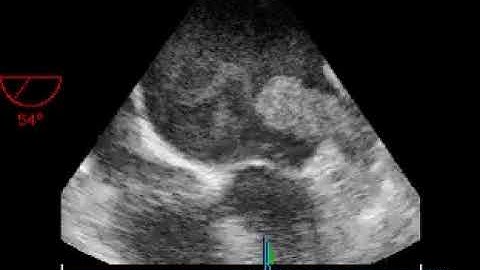

MS different aspects:left atrial appendage thrombus .TEE